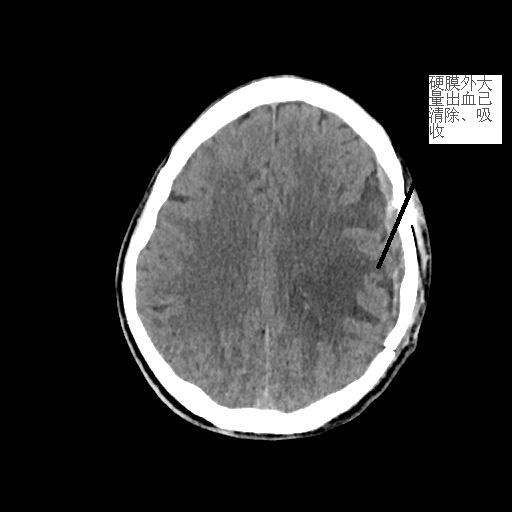

患者潘先生,因騎車摔倒入院搶救。入院時(shí),潘先生神志已模糊,無法對(duì)答,檢查檢驗(yàn)提示顱內(nèi)多發(fā)損傷,出現(xiàn)腦疝,病情危重,我院神經(jīng)外科團(tuán)隊(duì)緊急聯(lián)系福醫(yī)大附二院當(dāng)日值班專家來院開展開顱手術(shù)。經(jīng)及時(shí)搶救,患者病情穩(wěn)定,轉(zhuǎn)危為安。

<<<< 治療前后對(duì)比